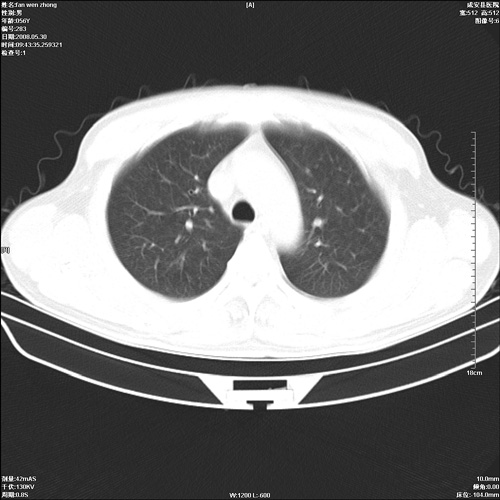

病人 男 56岁 一周前高热,体温达39-40度,经抗炎治疗后,体温渐降,达37,5-38度,轻微咳嗽,胸部不适 查白细胞为1.3万 行ct检查,请分析。

双肺内可见多发结节状病灶,并见小空洞,病人高热,白血球增高,应该是典型的迁徙性肺脓肿(多为金黄色葡萄球菌感染)。查一下口腔等其它部位有无感染灶。

双肺内可见多发结节状病灶,并见小空洞,病人高热,白血球增高,应该是典型的迁徙性肺脓肿(多为金黄色葡萄球菌感染)。建议治疗后复查.